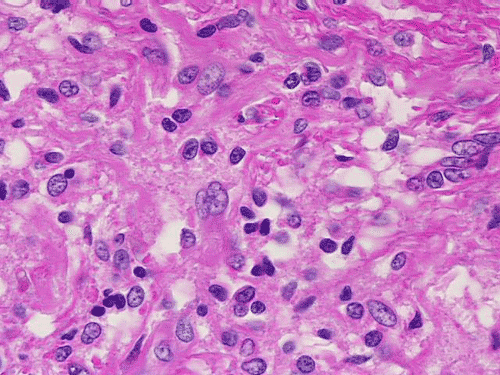

On low-magnification, cross section of the optic nerve gives a "double barrel" structure. The general outline of an optic nerve can still be appreciated (delimted by Þ in Panel A). There is a moderately cellular population of cells in between the dural sheath ( in Panel A) and the optic nerve. On medium-magnification, the vascular septa of the optic nerve is preserved (Panel B). On high-magnification, the optic nerve contains a mixture of cells with enlarged, mildly pleomorphic nuclei that are neoplastic astrocytes. Some cells with small nuclei are present and probably represent residual and reactive non-neoplastic astrocytes (Panel C and D). Cytoplasmic processes of some of tumor cells appear finely fibrillary (Panel C) while others are corase (Panel D). The cells in between the optic nerve and the dura is a mixture of irregular, hypercellular islands of neoplastic glial cells (delimted by Þ in Panel E) and hypocellular islands of slightly eosinophic, spindle cells. The later population represents reactive proliferation of meningothelial cells. The cytologic features are better appreciated in high-magnification (Panel F).

Microscopically, ONG in children are almost all pilocytic astrocytomas. The optic nerve is expanded. The fibrovascular septa within the optic nerve are separated by the tumor cells but the structure can still be well recognized as an optic nerve on cross section. Three major patterns are recognized 1. In the first pattern, the tumor is finely reticulated. In the second pattern, the tumor has microscysts and is coarsely reticulated. In the third pattern, the tumor cells are coarsely fibrillated, spindle shaped, and form bundles. There is minimal pleomorphism in the nuclei and it is not always easy to separate the neoplastic cells from adjacent reactive gliosis. There is a usually lack in mitotic activity, endothelial proliferation, and necrosis. Immunohistochemistry, the tumor cells are strongly reactive for glial fibrillary acidic protein (GFAP).

ONGs often extend into the subarachnoid space and inflict a prominent proliferation and thickening of perioptic meninges. This proliferation is composed of meningothelial cells, fibroblasts, and neoplastic astrocytes. Such changes are also known as arachnoidal hyperplasia or arachnoidal gliomatosis. The tumor tends to have coarsely fibrillated spindle cells may not be easily to be separated from the meningothelial cells and fibroblasts due to the intermingled architecture. Immunohistochemistry for GFAP is very helpful in separating the two components.